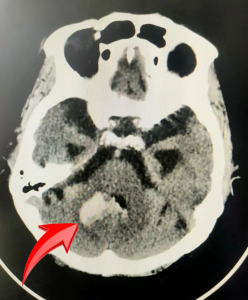

图一: C T显示右侧小脑出血病灶

接诊医生向医生在经过了一天忙碌的工作之后,马上集中精神接诊该患者,在内二区唐婉莹主任的指导下,通过临床表现、查体体征结合既往史,考虑急性脑血管意外,立即联系影像科行头颅和胸部CT检查,确诊为急性脑出血同时合并肺部感染,并及时制定治疗方案。